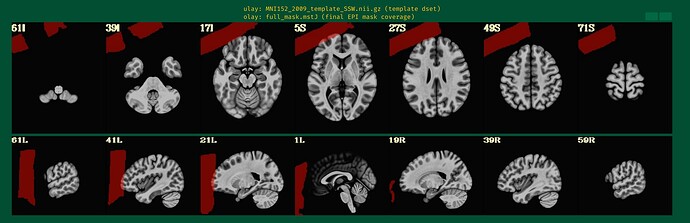

@djunct_overlap_check \

-ulay anat_final.s02+orig \

-olay final_epi_vr_base_min_outlier+orig \

-prefix img_olap

returned